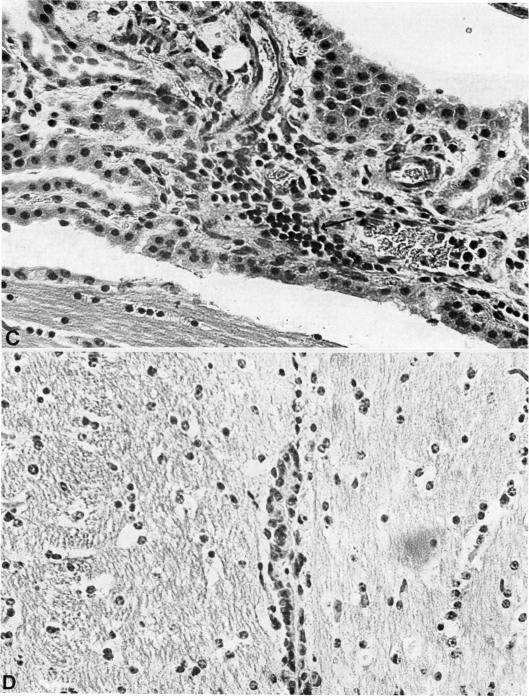

Groups of 4 guinea-pigs were immunized with acid extracts prepared from bovine myelin (EF), normal human liver tissue and malignant or benign neoplastic tissues in Freund's complete adjuvant (FCA1. The animals were weighed daily and examined for clinical signs of experimental allergic encephalomyelitis (EAE). All the animals immunized with EF developed clinical symptoms of EAE within 21 days of the initial immunization, whilst some of the animals immunized with certain tumour extracts developed symptoms which closely resembled those of EAE. Control animals immunized with FCA only remained asymptomatic. Cellular immunity to the various extracts in immunized animals was assessed 20 days after immunization by i.d. skin testing, and upon killing at Day 21 with the direct peritoneal-exudate macrophage migration inhibition (MMI) test. Brains and spinal cords were removed at killing, fixed in formalin and processed for histological examination. I.d. skin testing was shown to be most consistent in demonstrating positive delayed hypersensitivity, whilst the MMI test frequently gave negative results in the presence of pronounced skin responses to specific extracts. Thus it was shown that 3/4 animals immunized with basic proteins extracted from an adenocarcinoma of the lung or related hepatic metastases, and 1/2 animals immunized with an extract of a carcinoma of the breast, gave intense erythema and induration responses 5 mm in diameter 24 h after i.d. challenge with EF. No such response was obtained in animals immunized with basic proteins extracted from normal human liver, any of the other neoplastic tissues, or in control animals immunized with FCA only. Examination of brains and spinal cords from animals immunized with EF revealed dense infiltration by mononuclear cells in the ependyma and choroid plexus of levels in the spinal cord. Examination of brains and spinal cords from animals immunized with the lung-tumour extract or related hepatic metastases which showed demonstrable immunological cross-reactivity with EF in immunized animals, revealed a number of inflammatory changes characterized by dense infiltrates of mononuclear cells sub-ependymally, and perivascular cuffing in the cortex. However, no significant lesions were seen in the spinal cords of these animals. Polyacrylamide-gel electrophoresis of the 2 tumour extracts exerting this apparent encephalitogenic effect did not reveal proteins within the mol. wt range of EF. Thus the observed pathological effects and cross-reactivity with EF were probably not due to contamination with nervous-tissue components. It is suggested that these tumour extracts may have contained a component or components other than EF, immunologically cross-reactive with EF, and capable of inducing the observed encephalitis.